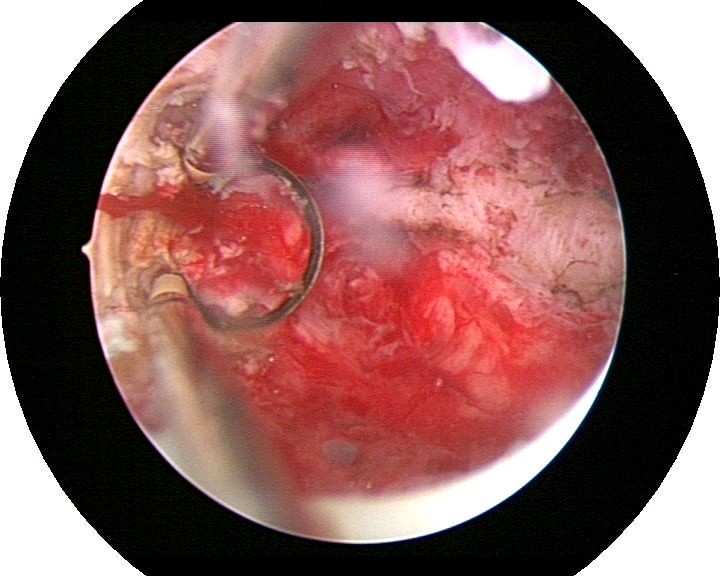

患者35岁,G4P0,2011年4月因继发不孕、月经减少2年,行宫腔镜探查,发现宫腔广泛重度粘连,单极电切分粘,恢复宫腔形态,显露双侧输卵管开口,放置节育环一个,术后月经恢复正常。2011年9月行宫腔镜二探并取环,O型环部分嵌顿,分离残留粘连,宫腔形态正常,双侧输卵管开口可见,同时行腹腔镜下左侧卵巢囊肿剥除术,术中通液双侧输卵管通畅。术后病人及爱人外出旅行,2个月后自然妊娠至足月,2012年7月要求我到其住院医院为其剖宫产,胎盘粘连,出血较多,手术顺利。现49岁,G5P1。